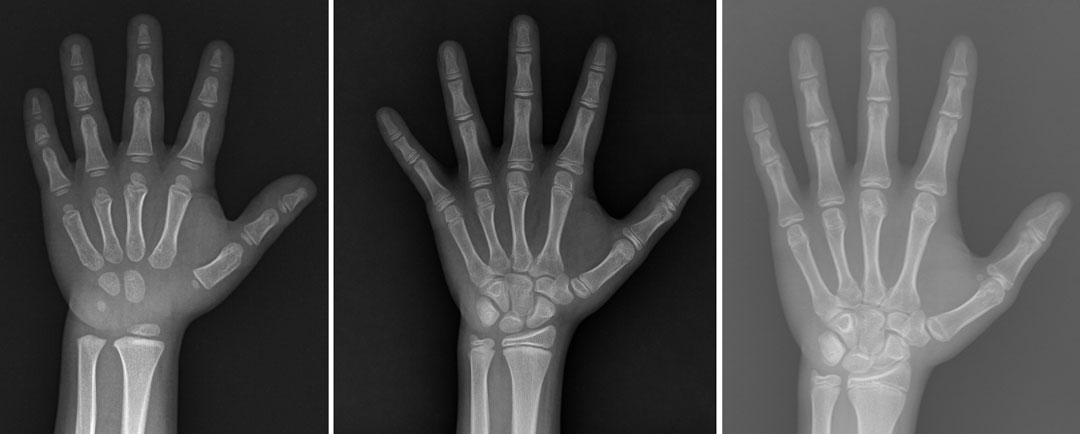

Q. 성장판 이란?

성장판은 전신에 분포되어 있는 뼈의 양쪽 끝에 위치하여 뼈가 자라 키를 크게 하는 장소

사춘기가 마무리되어가면 성장판이 모두 뼈로 바뀌게 되면서 길이 성장이 끝나게 됩니다

뼈 나이 측정